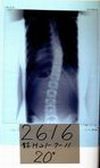

2002年11月

装具無し

立位30度-18度 |

順天堂大学装具

着用

23度-16度 |

2002年12月

大塚整体指導装具

10度-8度 |